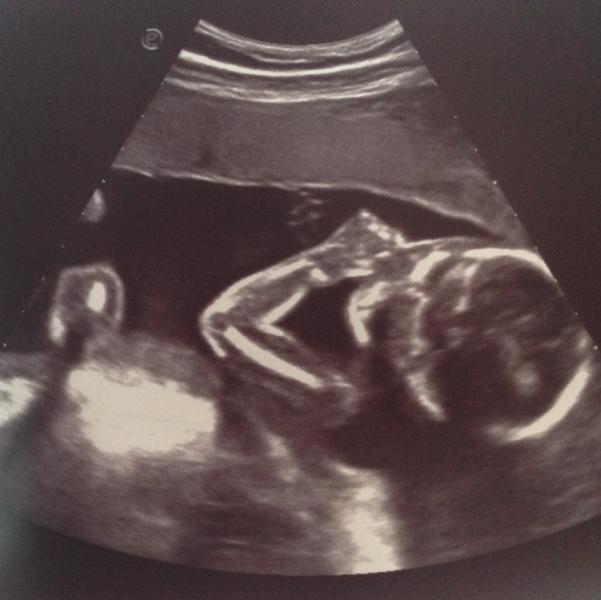

👇🏻Предлежание - головное

➰Обвитие - однократное

👶🏻Пол - мальчик

💪🏼Вес - 3676

📏Рост - 53